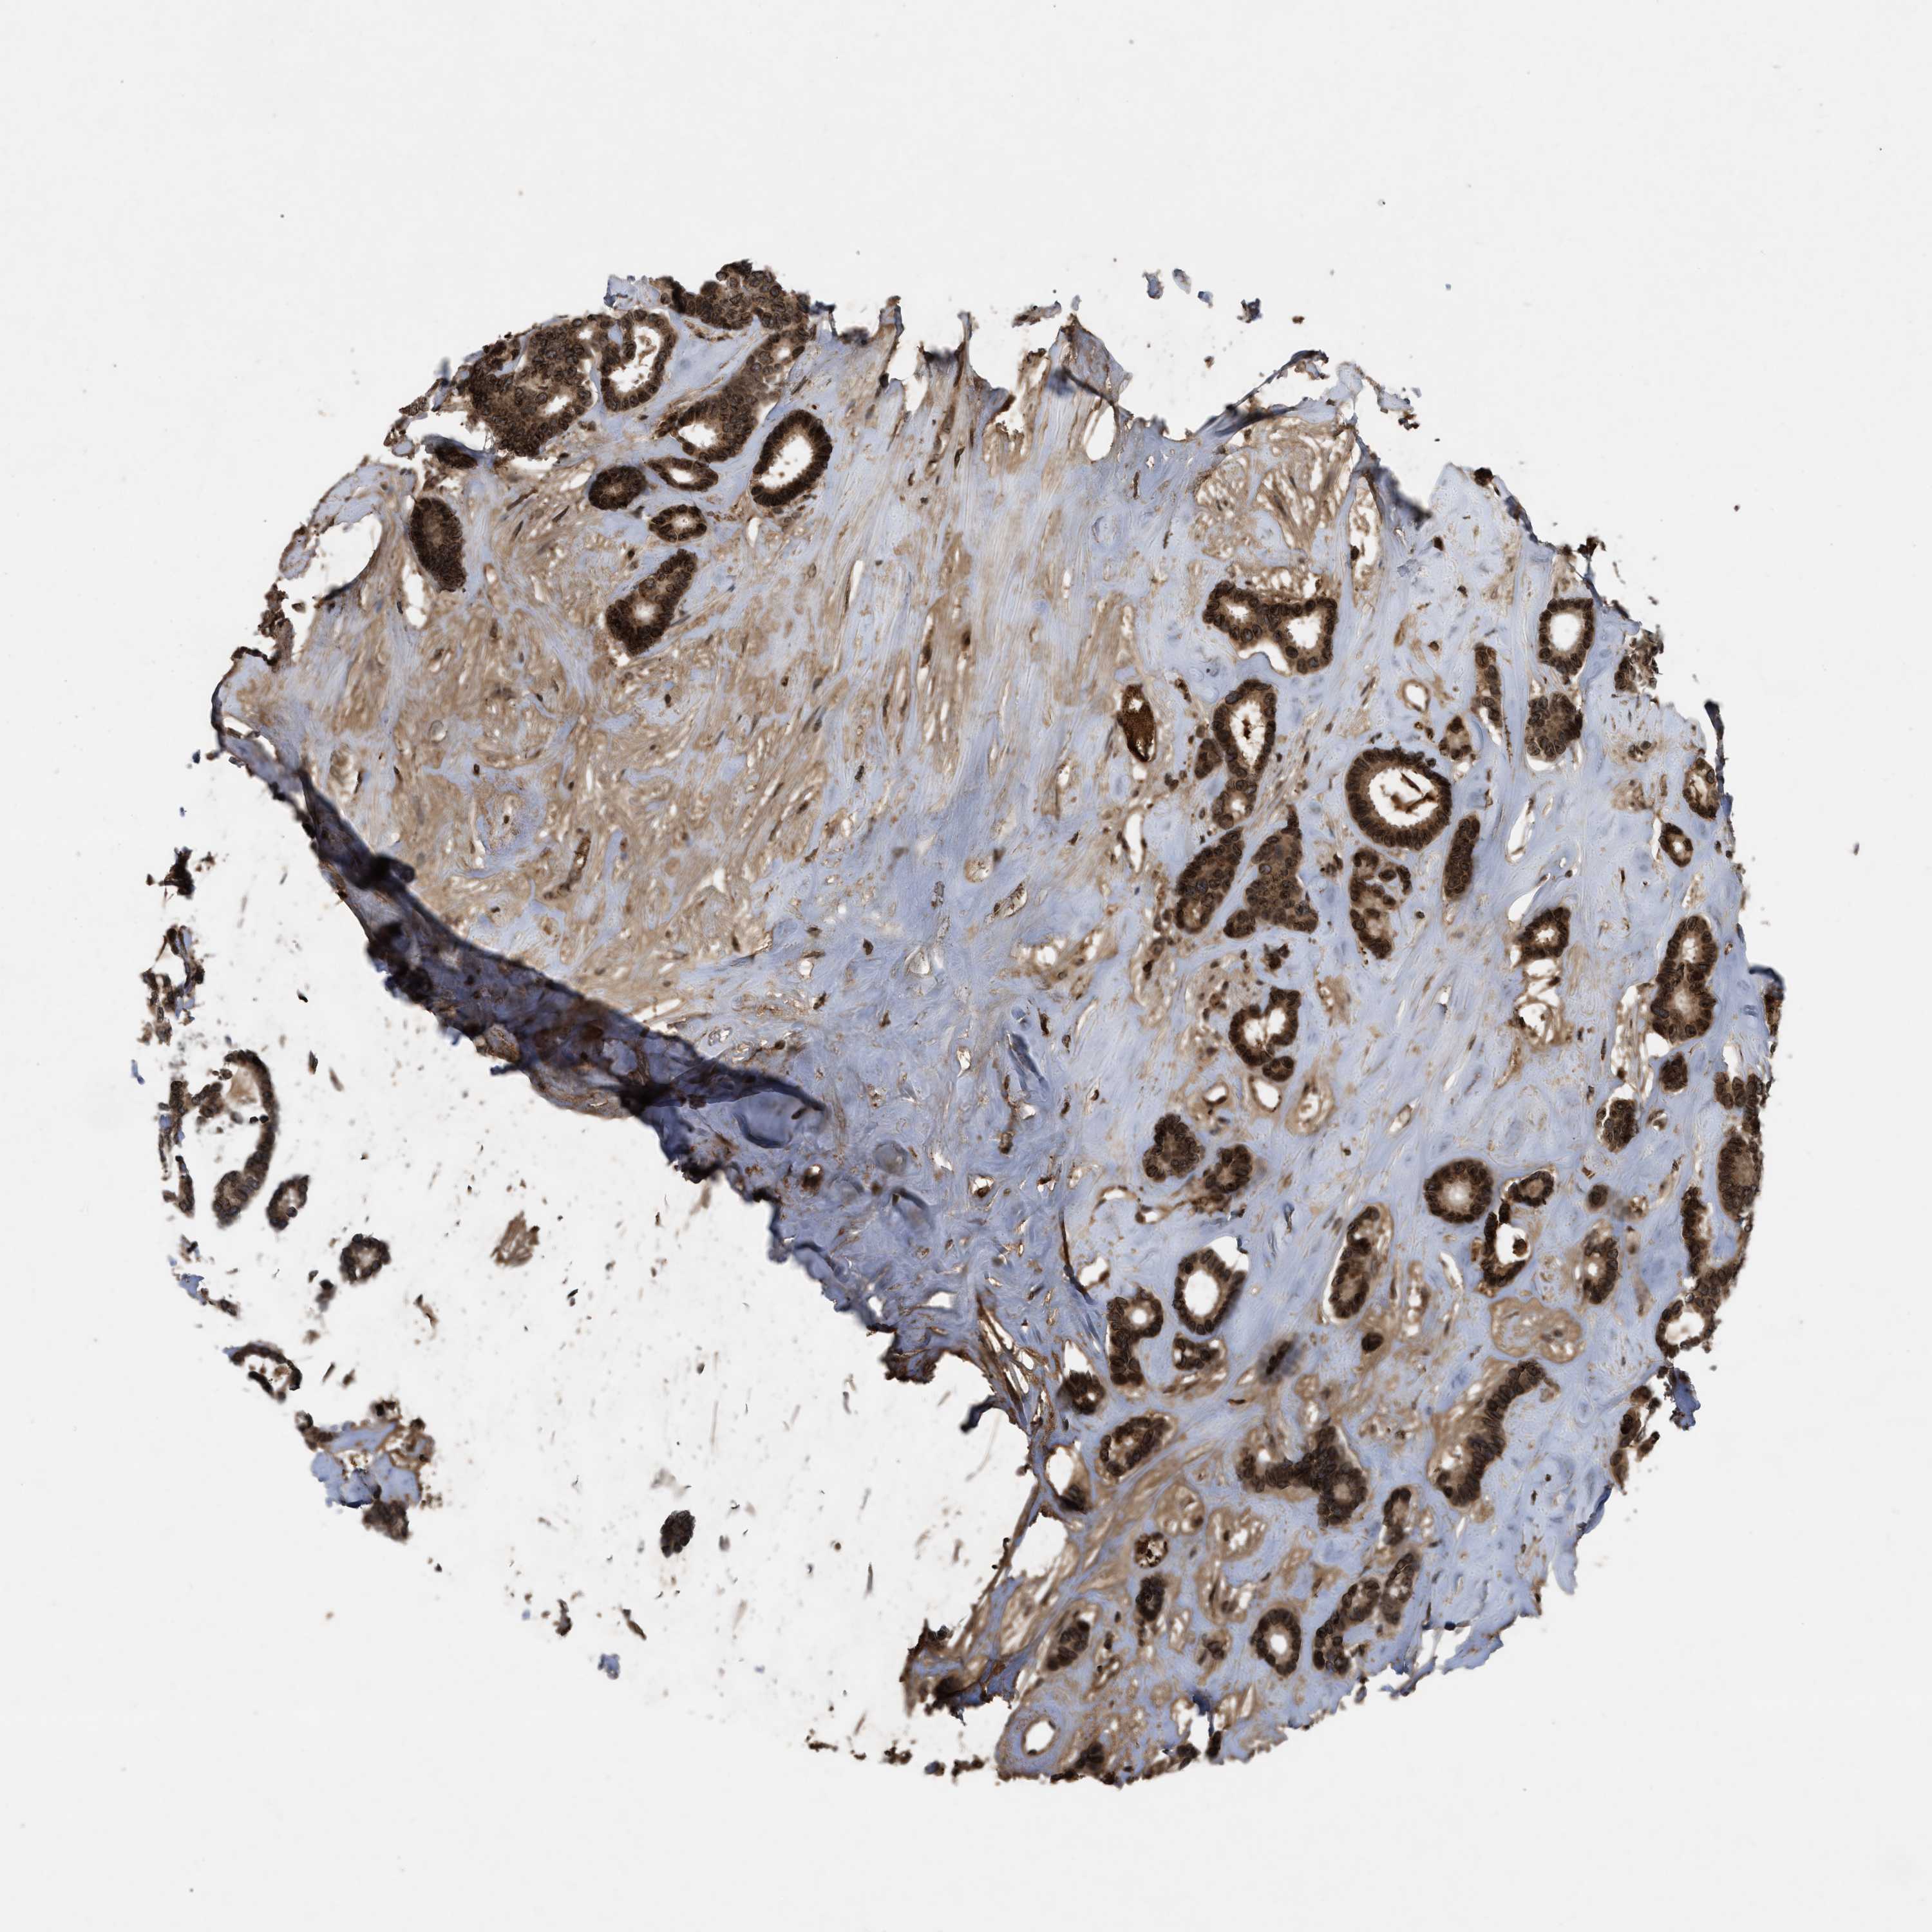

BRCA TCGA BRCA VALIDATION PROTEIN EXPRESSION